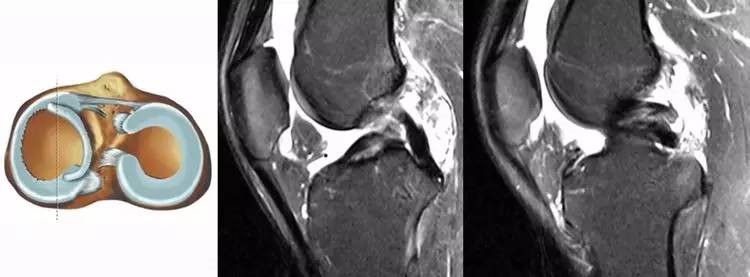

9.内侧半月板后角撕裂:内侧半月板后角是ACL的重要稳定结构,一旦发现青壮年患者的内侧半月板后角损伤,应该高度怀疑是ACL的继发损伤。常常见于陈旧损伤患者。

22.jpg

10.外侧半月板后根损伤:外侧半月板后根撕裂的受机制与ACL损伤的机制相似,因此发现外侧半月板后根损伤时必须考虑有ACL损伤的可能性。

23.jpg

11.半月板桶柄状撕裂:为膝关节的一种严重损伤,常伴有ACL损伤。

24.jpg